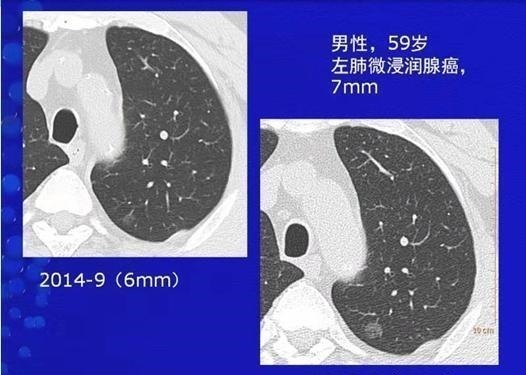

这是一位59岁的男士,体检发现左肺纯磨玻璃结节,直径6mm,随访观察逐渐增大,9个月后增大到9mm,手术病理是浸润性肺腺癌。例2,磨玻璃结节,增长迅速,病理为浸润性肺腺癌